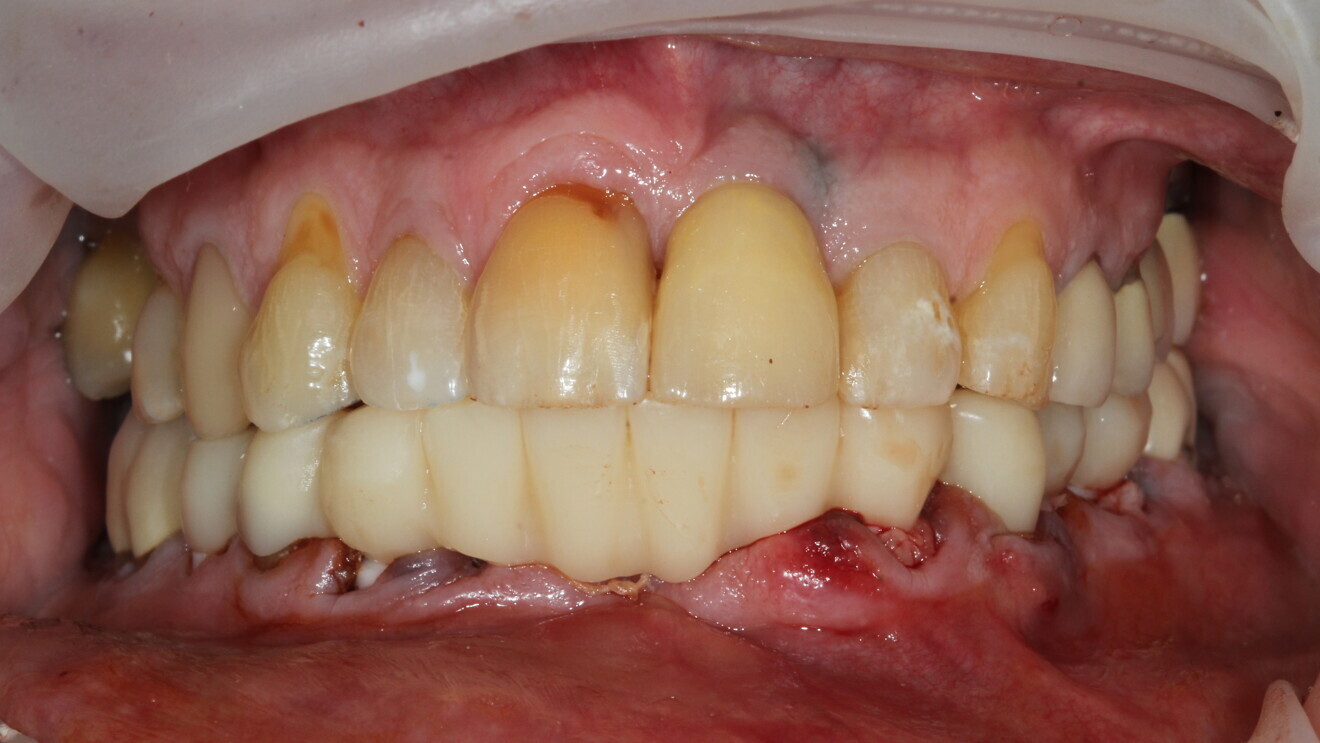

Fig. 9: Temporary restoration in situ.

Digital impressions were taken with CEREC Primescan (Fig. 7) and sent to the laboratory for same-day fabrication of the temporary restoration (Flexcera Smile Ultra+, Desktop Metal; Fig. 8). Suturing was completed, and the full-arch temporary restoration was adjusted and seated with temporary cement (Fig. 9).